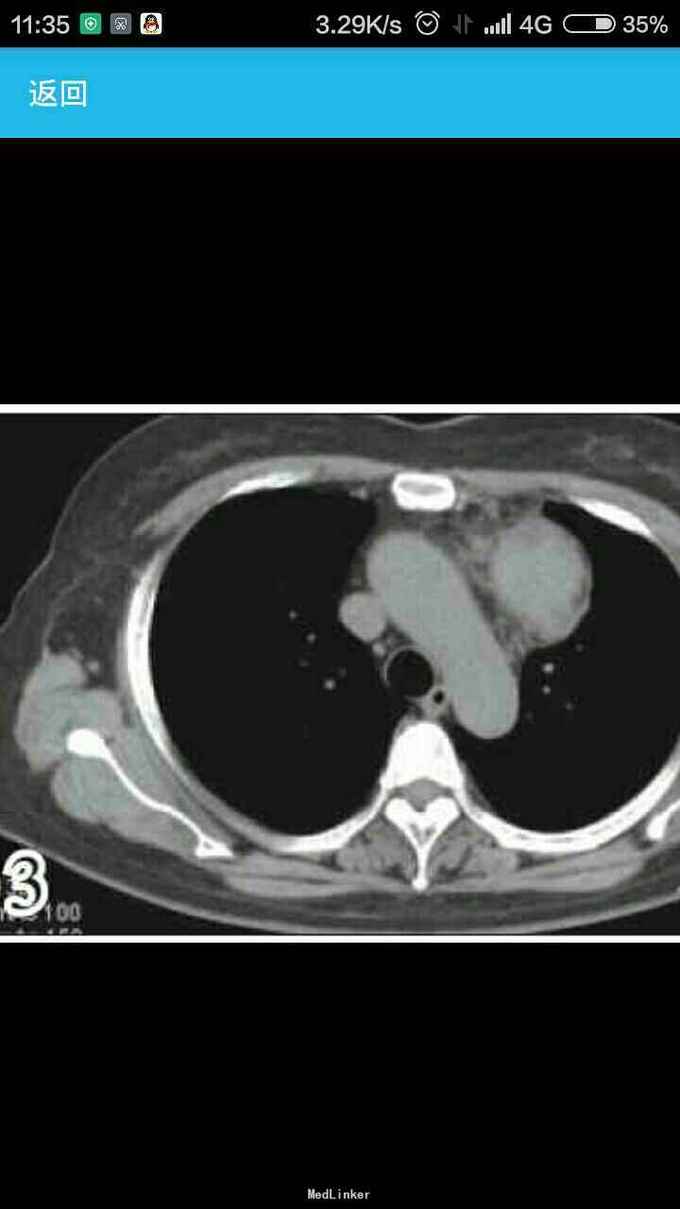

女性,60岁,因左 趾关节红肿、剧痛,红肿弥漫足背 23天来诊,不伴发热,无外伤史, 全身体检无明显异常。 胸片示,左侧前上纵隔占位性病变(图1)。胸部CT示,左侧前上纵隔内见5.7 cm×3.8 cm软组织肿块影,内见斑片状稍高密度影,境界不清(图2——5)。 实验室检查显示,血尿酸517.1 μmol/L(正常值180——357 μmol/L),临床诊断为“急性痛风”,为排除相关疾病作进一步检查。 印象:左侧前上纵隔占位(恶性肿瘤?畸胎瘤?)。 手术结果:肿瘤位于左前纵隔,大小约为8 cm×8 cm ×6 cm,质硬,表面光滑,与心包、无名静脉、肺门粘连(侵犯壁层、脏层、胸膜、肺门、心包、膈肌、膈神经,伴肿大淋巴结)。【病理结果示】(图6):肿块9 cm×6 cm×4 cm,侵犯周围脂肪组织,伴神经内分泌分化。肿块标记:CD5(+)、CD117(+)、嗜铬粒蛋白A(CgA)灶(+)、突触素(Syn,+)、CD56 (-)、细胞增殖因子Ki-67约20%(+)。【诊断】胸腺鳞状细胞癌Ⅱ——Ⅲ级,伴神经内分泌分化。